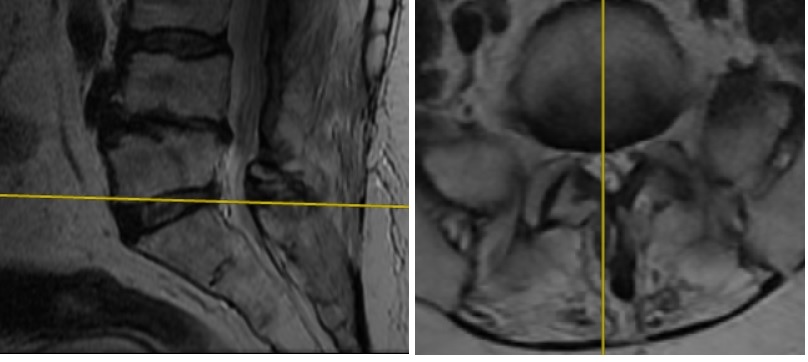

Postop AP Radyolojik Görüntü Postop Lateral Radyolojik Görüntü

Resim 7: Ameliyat sonrası (postop) direkt grafiler. PEEK rod ile dinamik stabilizasyon uygulanmıştır.

Ameliyatta eski ensizyon açılarak titanyum rodlar çıkartıldı. L4-5 seviyesi açılarak kanal içi ve foramen çıkışları dekomprese edildi. Disk içi boşaltılarak otojen kemik greft ile dolduruldu. Gevşemiş L4 ve L5 vidaları çıkartıldı. L4 vidaları kalın vidalarla değiştirildi, L5 seviyesine vida konmadı. S1 ve S2 seviyelerine vida kondu (S1 medial ve kaudal yönelimli, S2 vidaları laterale ve kraniuma yönelimli). L2 vidalarından S2 vidalarına uzanan birer PEEK rod ile sistem stabilize edildi.